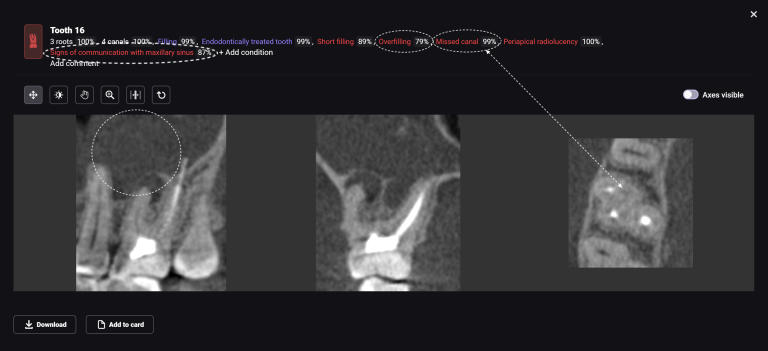

In order to predict the prognosis of the tooth, data from the Diagnocat radiological report and visualization capabilities of the 3D-Viewer tool were utilized, in addition to a clinical examination

The planning of immediate implant placement using Diagnocat AI has many advantages for both the doctor and the patient. Let’s consider them using a clinical case example, in which the removal of tooth 25 (Universal 13) and subsequent implant placement were planned